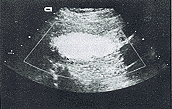

图1 左髂总动脉呈梭形扩张,管腔

血流充盈良好,未见充盈缺损。